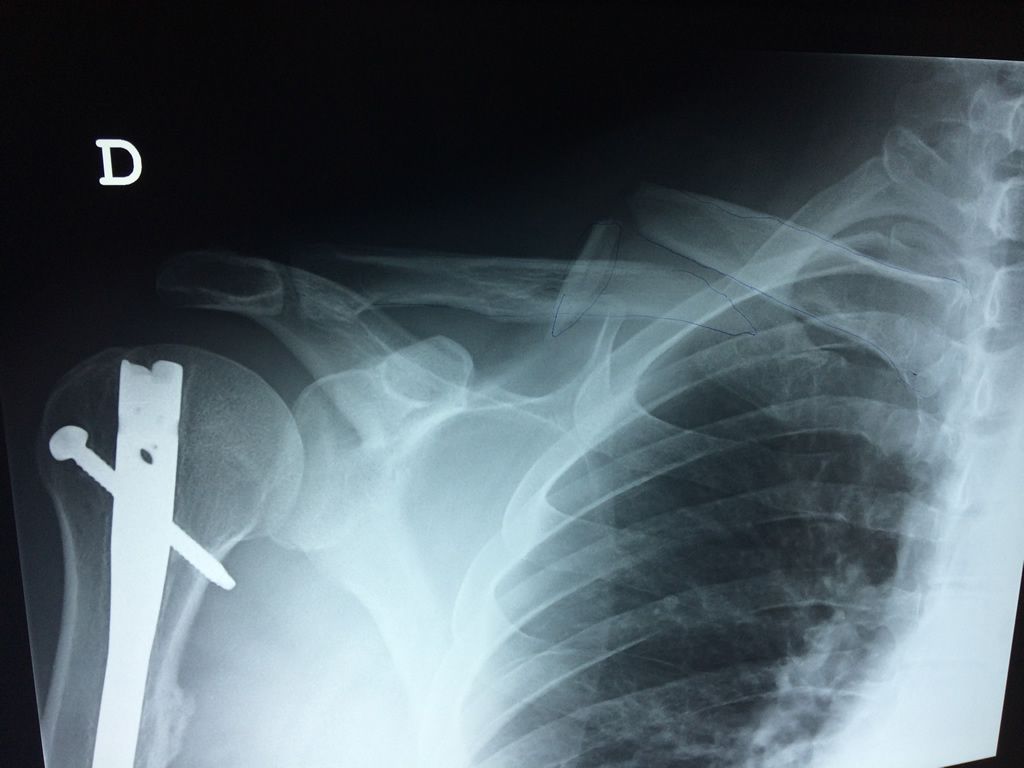

Cirugías de Hombros - Clavícula

La clavícula es un hueso largo, con forma de "S" itálica, situado en la parte anterosuperior del tórax. Junto con la escápula forman la cintura escapular. Se puede palpar por toda su longitud y se extiende del esternón al acromion de la escápula, siguiendo una dirección oblicua lateral y posterior.

Se considera el único medio de unión entre el miembro superior y el tórax. A pesar de su aspecto, similar al de un hueso largo, posee una estructura semejante a la de un hueso plano, ya que carece de epífisis y de diáfisis, lo que la harían entrar dentro de la clasificación de hueso largo. Carece de un canal medular propiamente dicho.